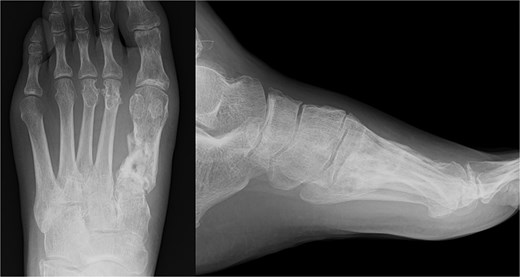

The external fixator was removed 4 weeks after the first surgery. Full weight-bearing was allowed 6 weeks after the operation. The plate was removed after confirming bone union. The patient was able to return to agricultural work 6 months postoperatively, and the American Orthopedic Foot and Ankle Society score 1 year post-surgery was 84. The follow-up radiography image taken at this stage is shown in Fig. 4.

Radiography (a, b) and computed tomography (c) images immediately after the second surgery.